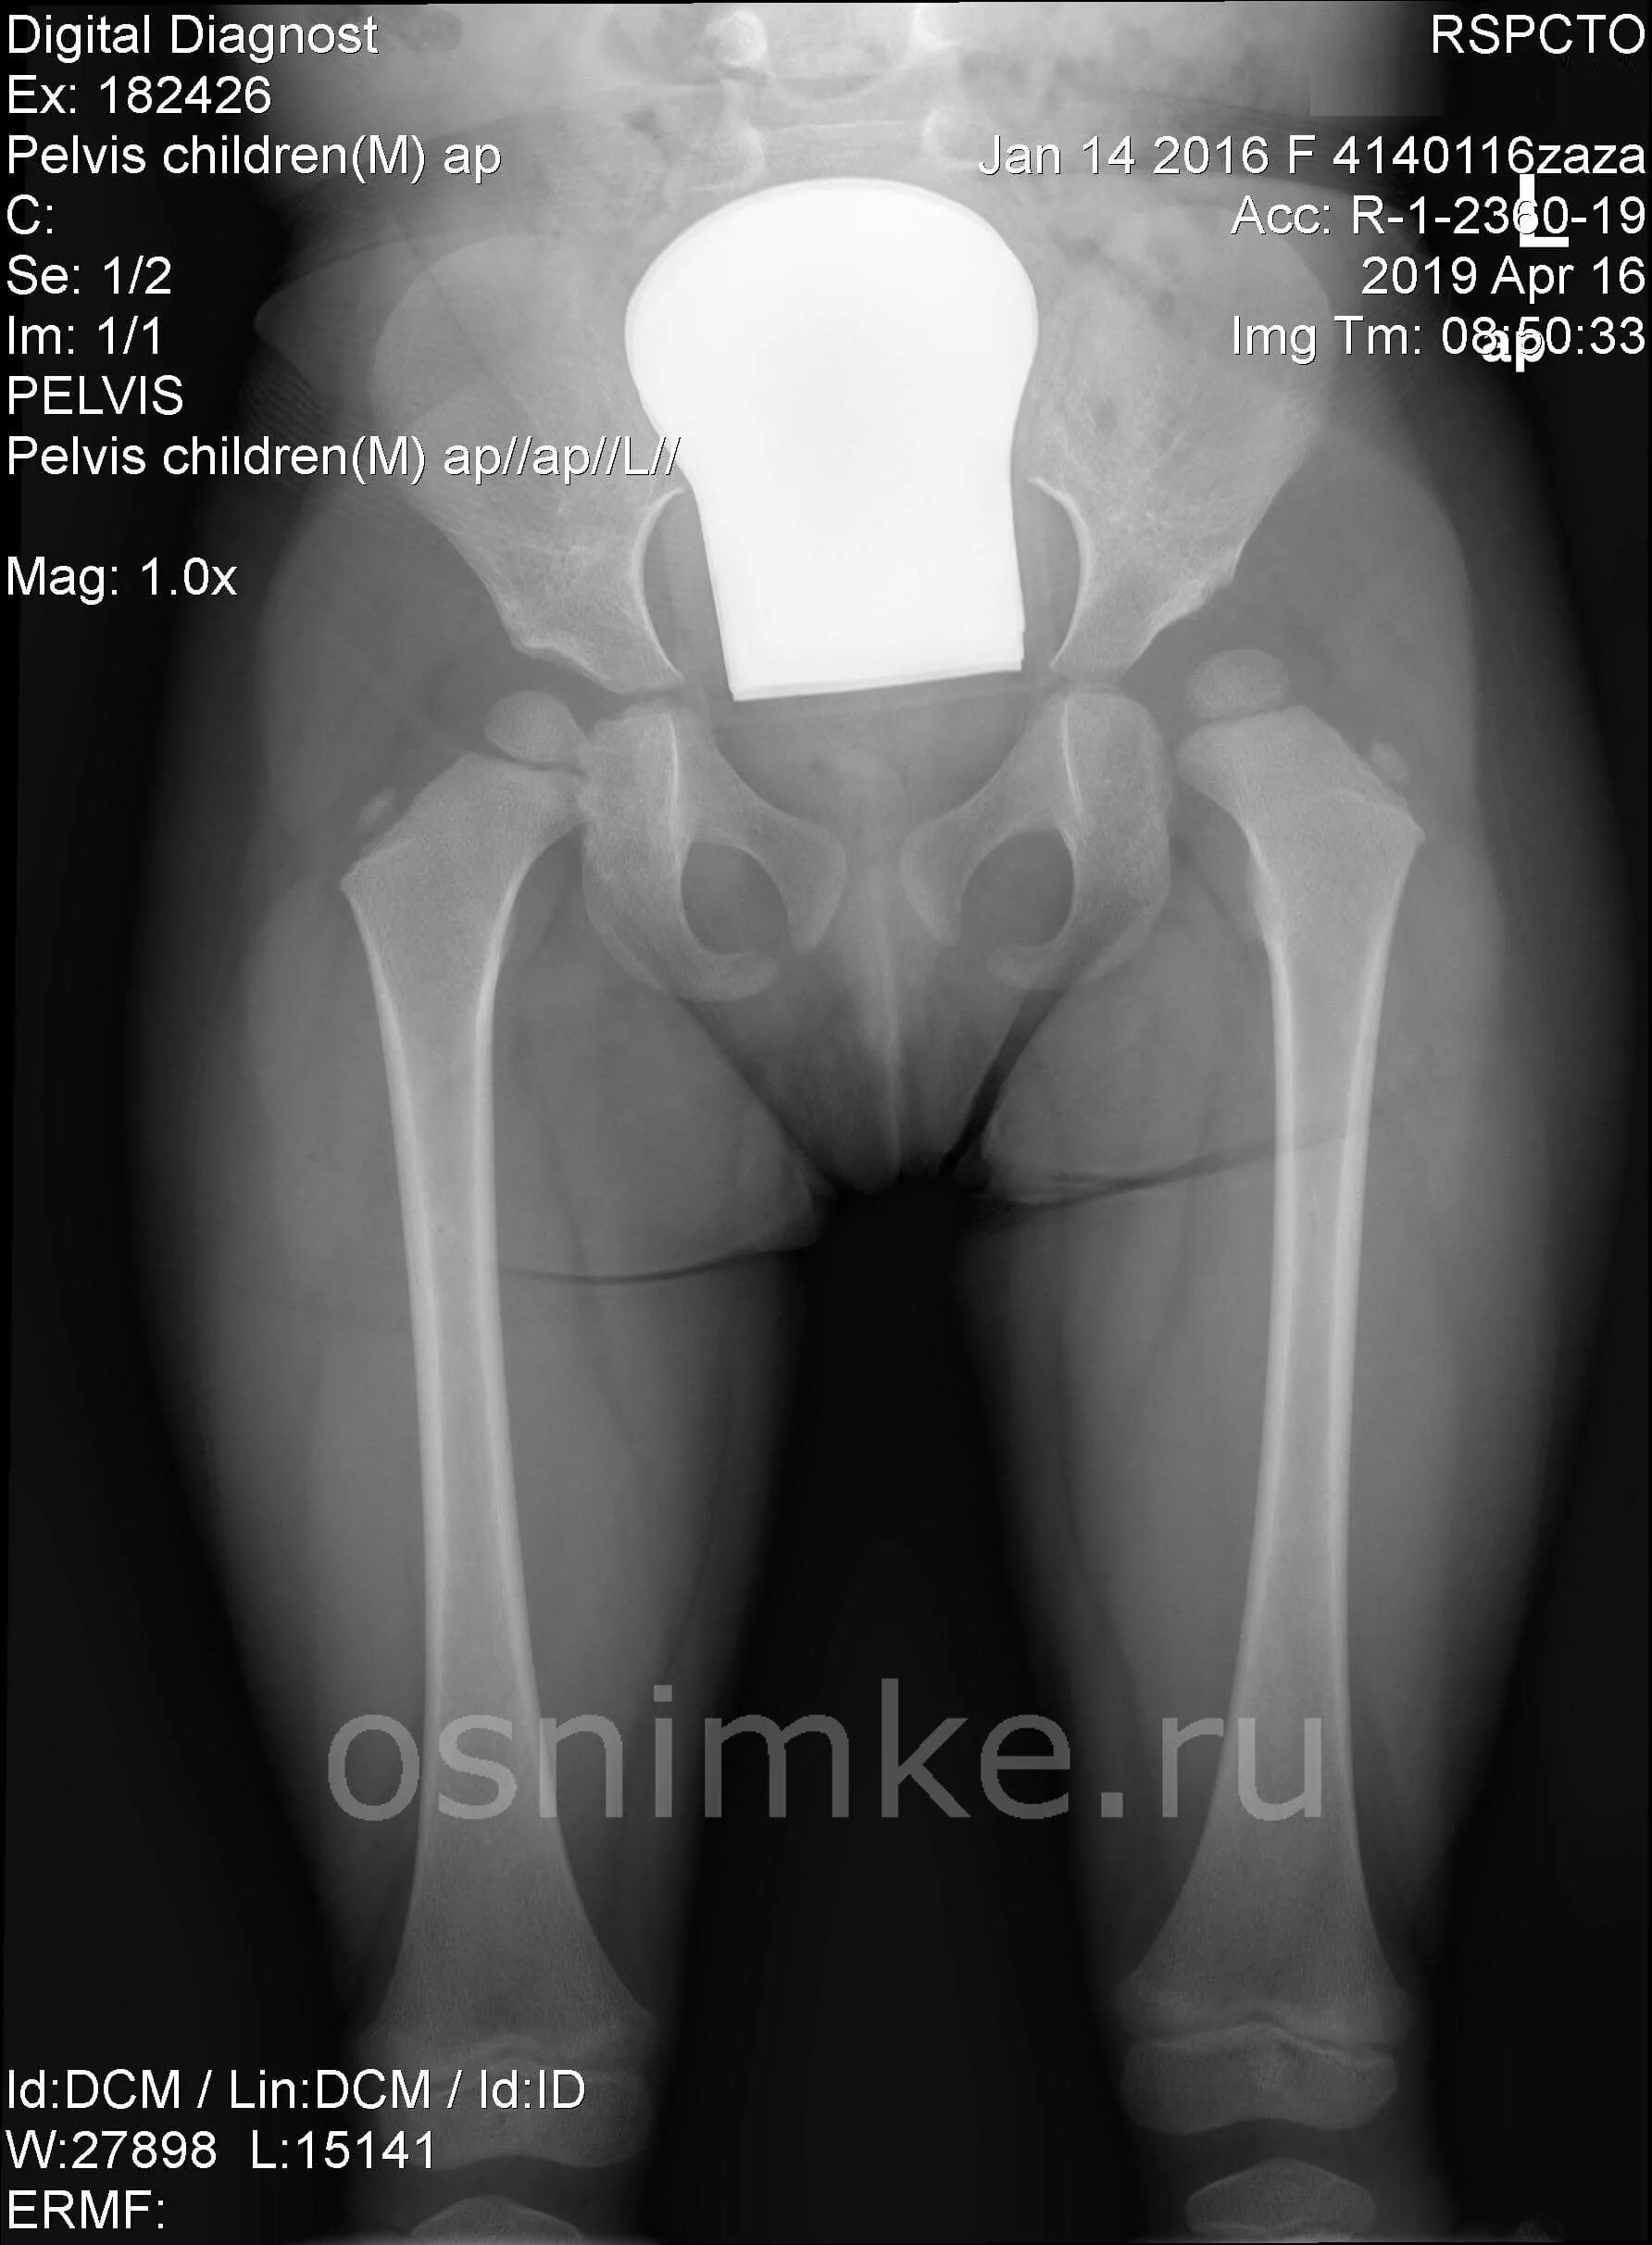

Вывих бедра тест